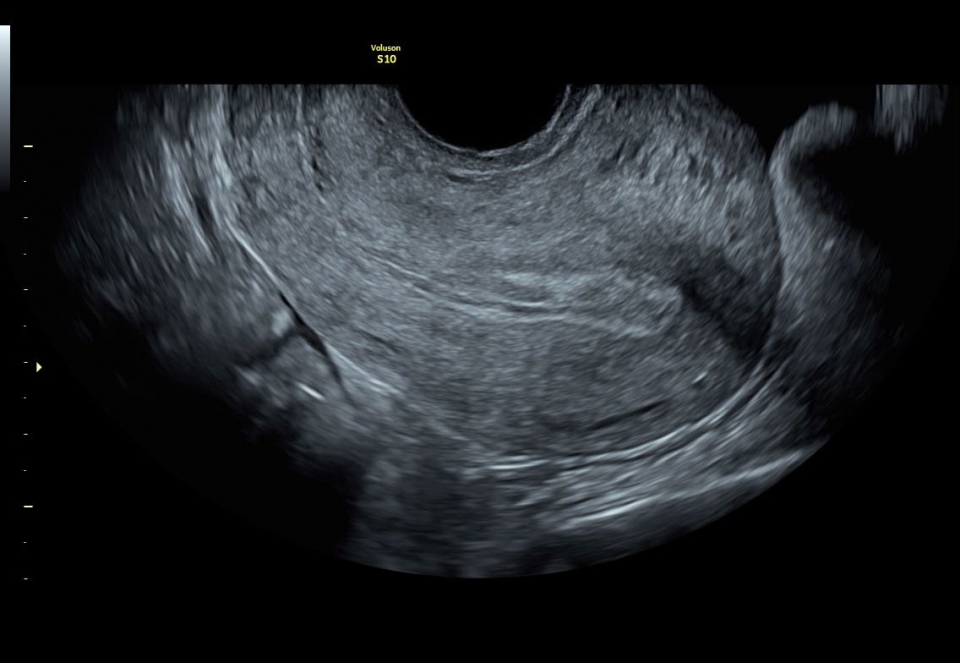

УЗИ аппарат Voluson S10 позволяет проводить обследования высочайшего уровня с максимальной точностью диагностики. Благодаря технологии Voluson Core Architecture достигнут высокий уровень качества изображений с возможностью последующей обработки и анализа даже после проведения скрининга. Технология HDlive делает изображения удивительно реалистичными и объемными.

Ультразвуковой аппарат Voluson S10 оснащен чувствительным цветовым допплером, который позволяет оценить кровоток и анатомию сосудов, обеспечивая полную информацию о состоянии плода и околоплодной жидкости. Кроме того, на Voluson S10 установлен большой 22-дюймовый экран, который при использовании трехмерного шарнира может поворачиваться в различных плоскостях, обеспечивая удобство как для пациента, так и для врача.

• Качественная диагностика: Благодаря высокотехнологичной платформе и инновационным технологиям, система обеспечивает высокое качество визуализации и быстрое получение объемных изображений, что позволяет врачам устанавливать точные диагнозы.